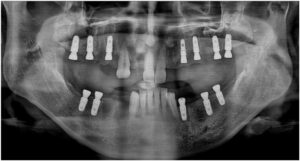

정밀한 검사를 위해

파노라마 사진을

촬영해 보았더니

치아를 단단하게 잡고 있어야 할 잇몸뼈가

녹아내려앉아있고,

염증이 있는 치아들도 다수 보였는데요.

양산전체임플란트를 진행하기에 앞서

파노라마 사진과 3D CT 촬영을 통해

잔존 치조골의 양과 두께,

상악동과의 거리, 하치조 신경의 위치,

눈에 보이지 않는 해부학적 구조물 등을

면밀하게 파악하는 과정을 통해

임플란트를 식립하기 좋은 위치와

식립 될 Fixture의 길이와

두께를 선정하였으며,